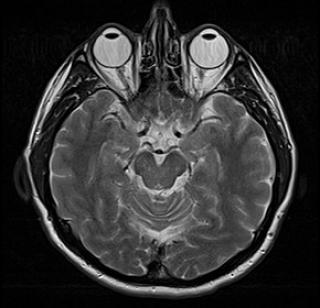

Плазмоцитома и амилоидоз сердцау женщины 60 лет. Т1 -взвешенная последовательность с подавлением жировой ткани с темнойкровью GE: Четырехкамерный срез демонстрируетвыраженную гипертрофию миокарда во всех участках стенки. Стрелки показывают разделение слоевперикарда в связи с наличием перикардиальноговыпота.

Последовательность обратного восстановления GE после введения Gd-DTPA. Четырехкамерный срез демонстрирует диффузное усилениевсех участков стенки.